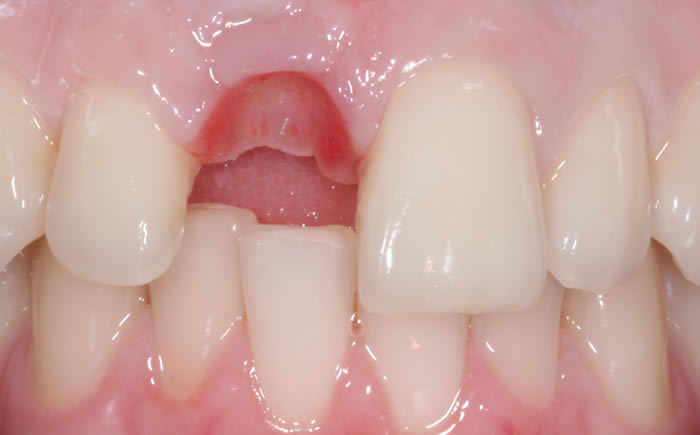

Before & After Gallery

More front teeth replaced by dental implants

Case Three (4 images)